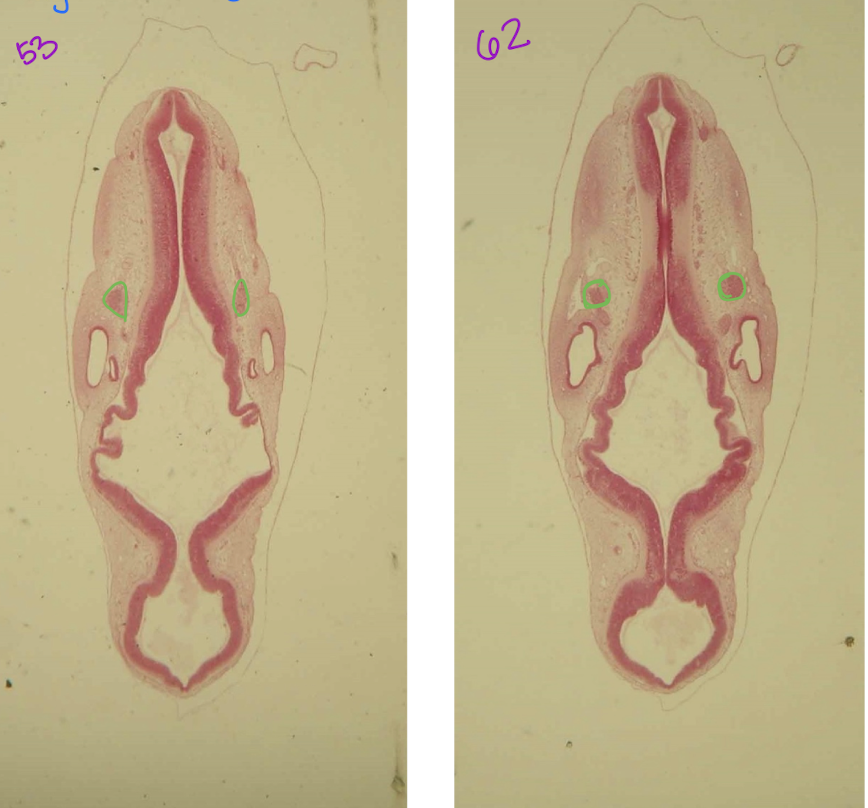

intersegmental artery branched of dorsal aortae, contribute to vertebral, subclavian, intercostal and lumbar arteries